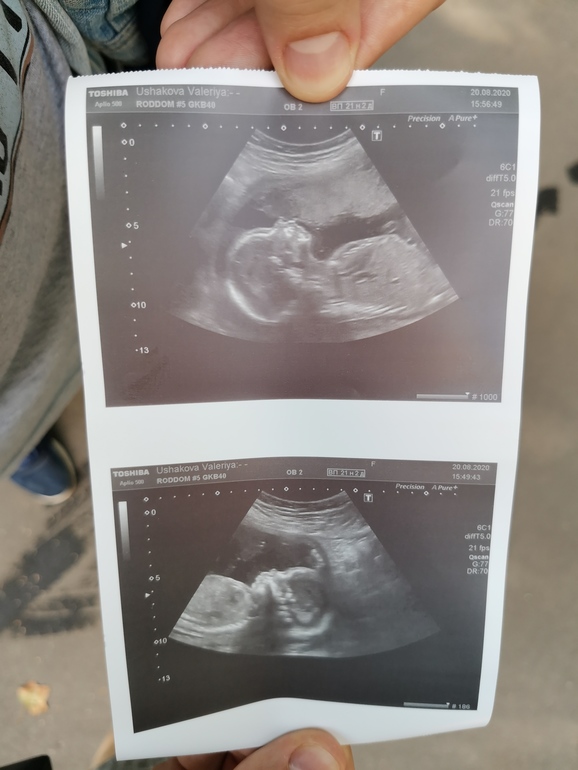

Второй скрининг пройден🥰✅

Сын остался сыном😁 Соответствует сроку, 20.2) Сладкий мальчик 350 гр, развивается правильно, всё у него хорошо🙏

Активничал там, махал ручками, открывал ротик, высовывал язык))

Протокол подробный на руки не выдали, скоро в жк у врача посмотрю)